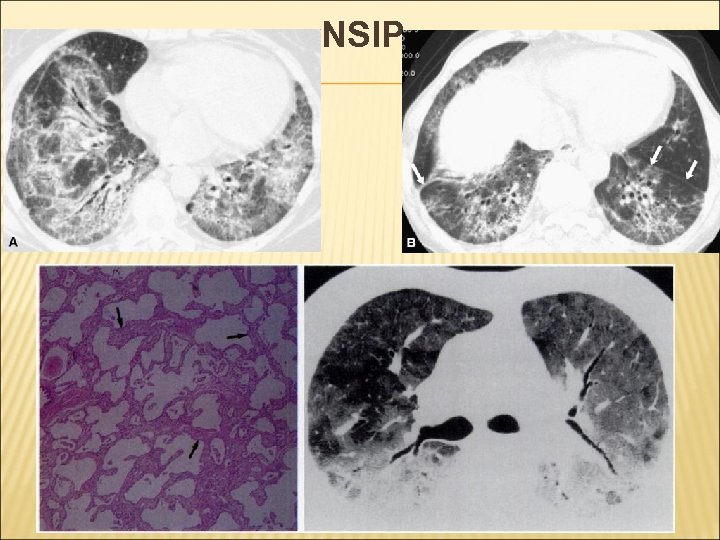

2. НЕСПЕЦИФИЧНА ИНТЕРСТИЦИАЛНА ПНЕВМОНИЯ - NSIP HRCT: Обширни промени “матово стъкло”, свързани с ретикуларни повлекла. КЛИНИЧНО: • Средна продължителност на симптомите преди диагнозата – 18 -32 мес. ; • Диспнея, кашлица и загуба на тегло средно 6 kg. ; • Инспираторни пукания и “писукания”; • По-добра прогназа в сравнение с IPF;

NSIP